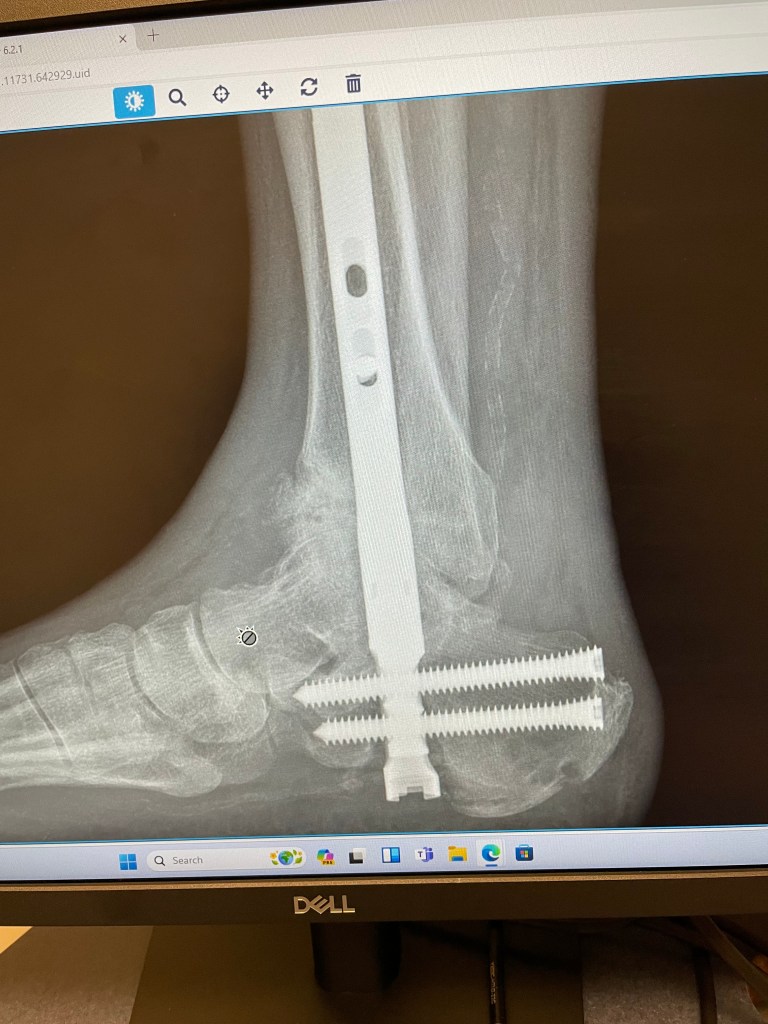

Here are some x-rays of my foot:

From top left to bottom, the dates are:

• February 7, 2024

• April 22, 2024

• May 13, 2024

• Today, May 20, 2024

You can see clearly that my ankle is dislocating downwards in the front. There is a growing hole right before you get to the toe bones. The problem was apparent on the May 13th x-ray, but much more obvious today. The other ankle surgeon at the office, a church friend, said that the bone is softer/weaker due to Charcot Foot, and usually that causes dislocations, fractures, and bone disintegration. By giving me another non-weight bearing cast, they hope to stabilize the ankle, and have it try to heal on its own.

Based on my luck so far, that is not likely. I will probably need more surgeries, including external fixators on the foot/ankle again. In the meantime, we are still waiting for another CT scan to get more clarity on what is happening.